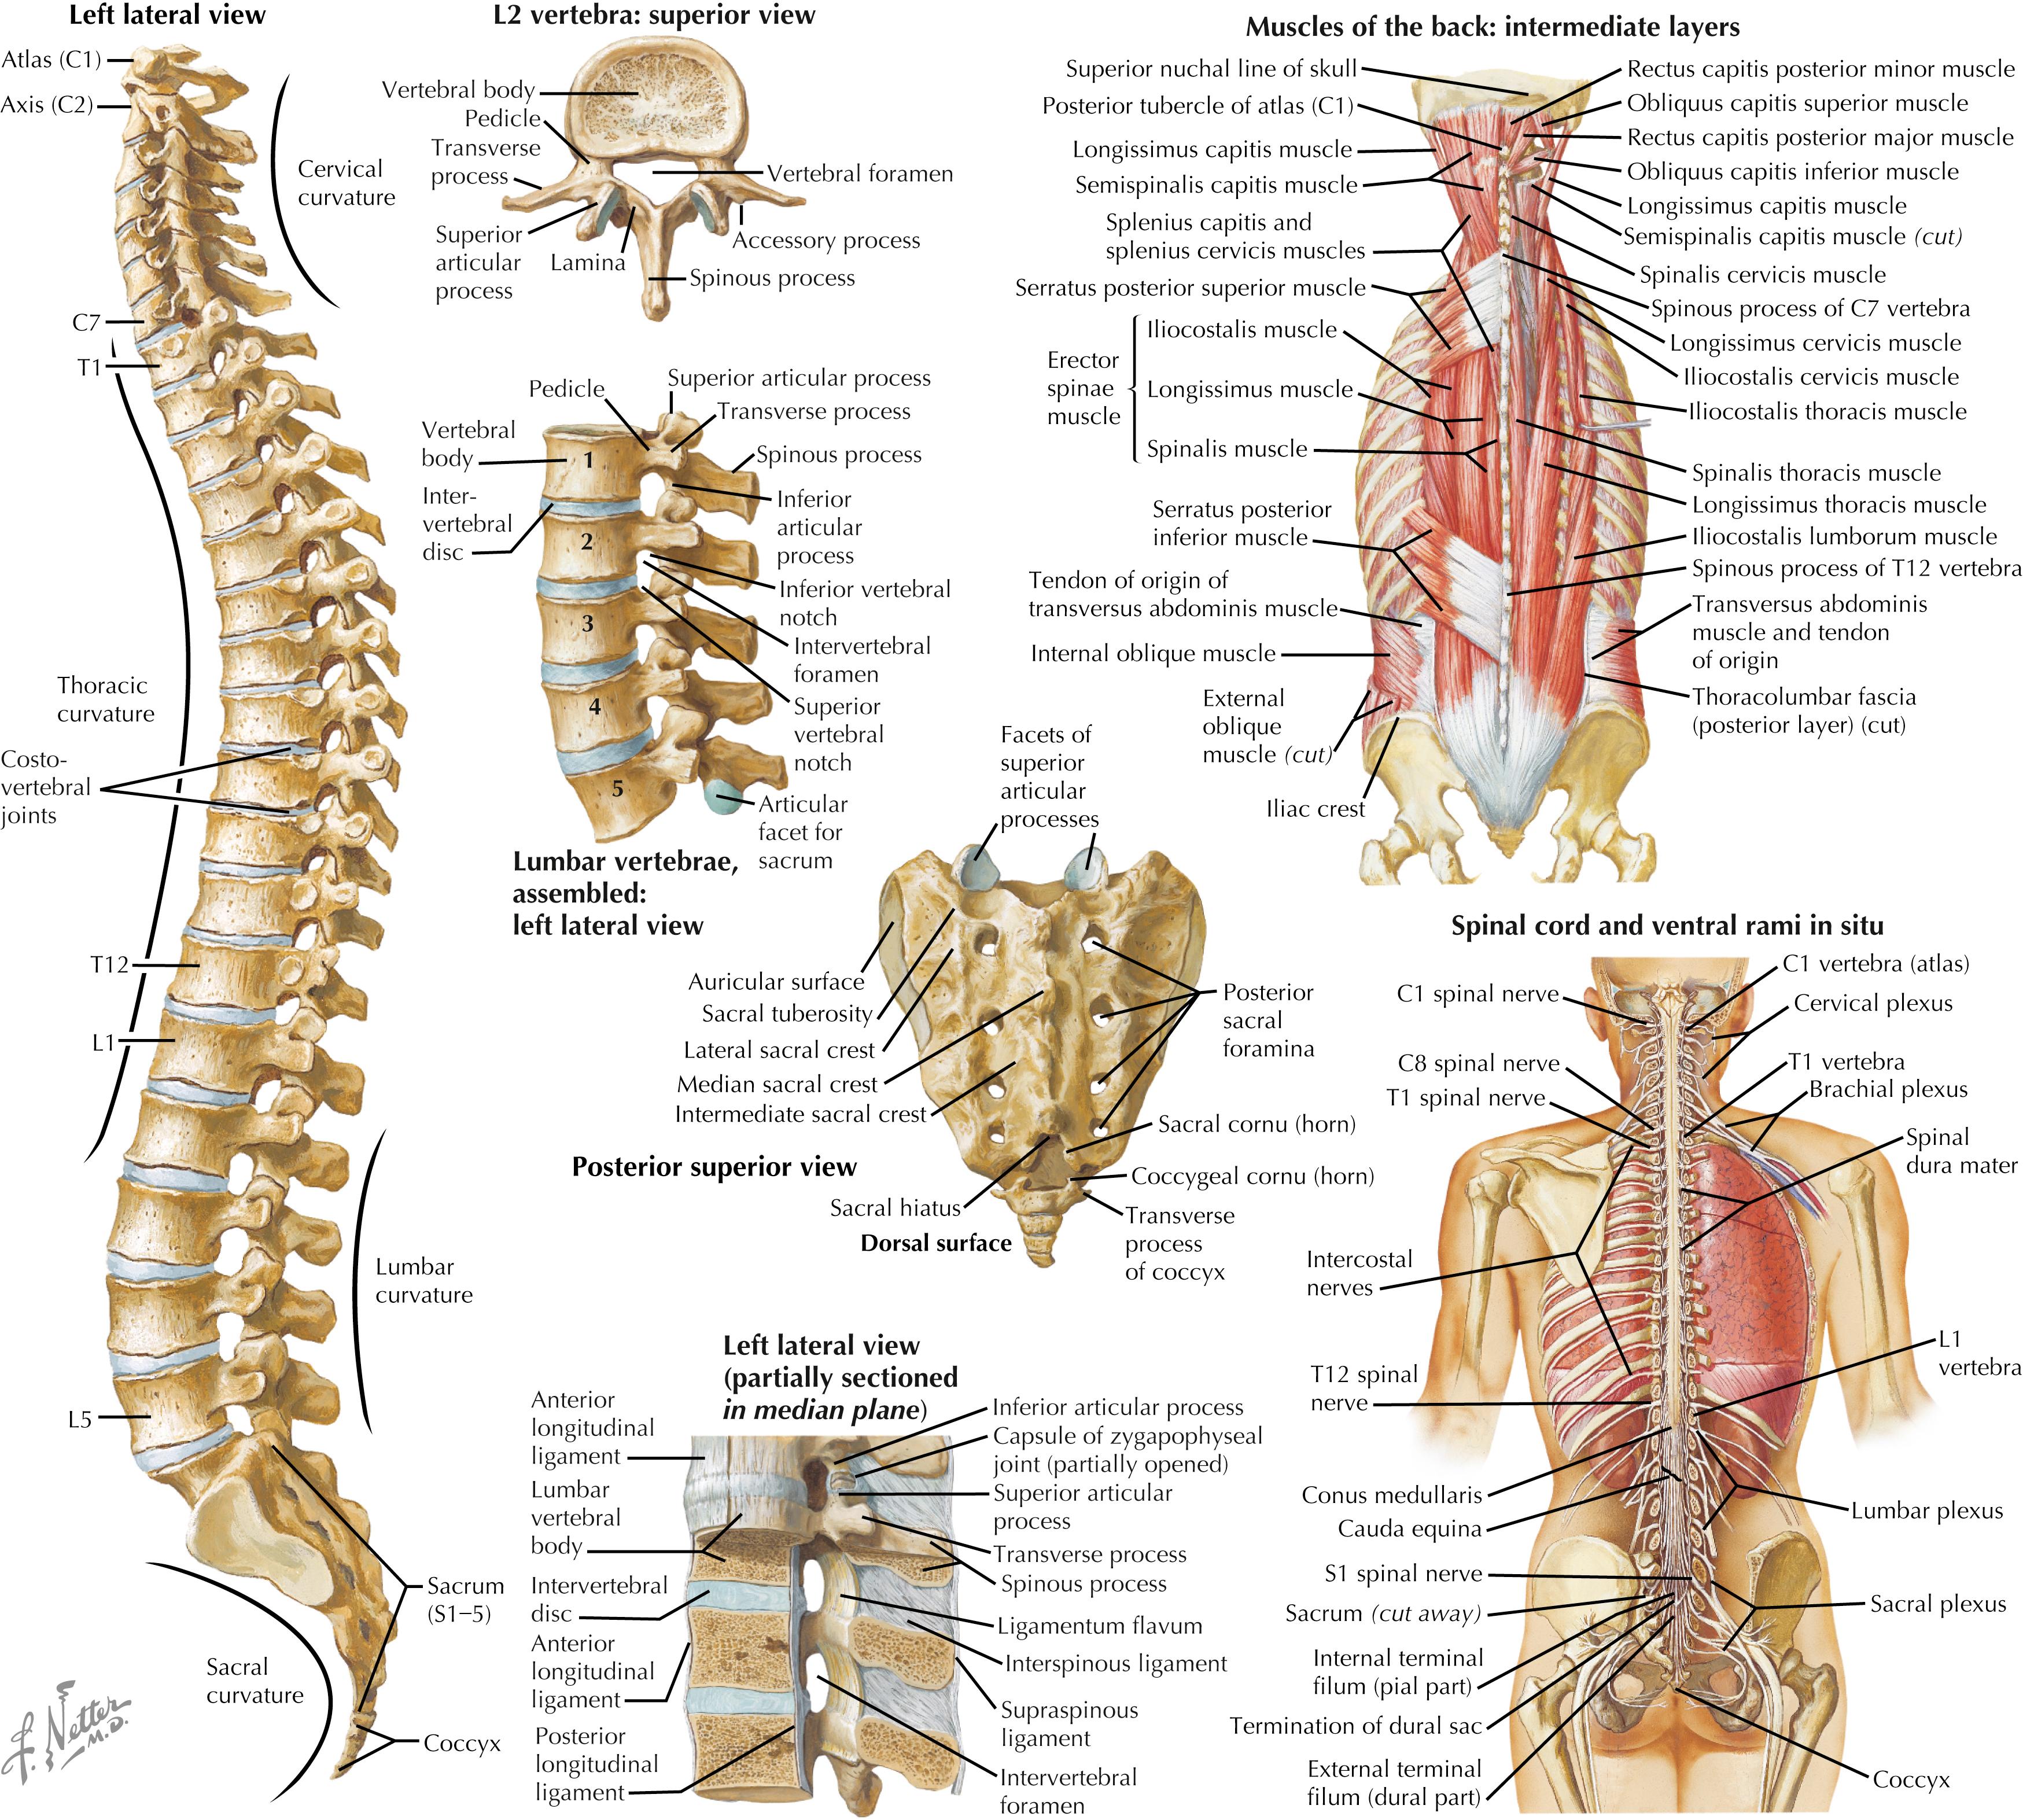

The Supraspinous and Interspinous Ligaments of the Lumbar Spine (circa 1978). – Husson U PT blog

Pure Health - Anatomy 101 - Supraspinous ligament and interspinous ligament 📚 The supraspinous ligament and interspinous ligament work together to limit flexion of the spine by limiting separation of the spinous

DOCS - The interspinous ligament is located between the spinous processes of adjacent vertebrae in the spine. It extends from the base of one spinous process to the apex of the next,